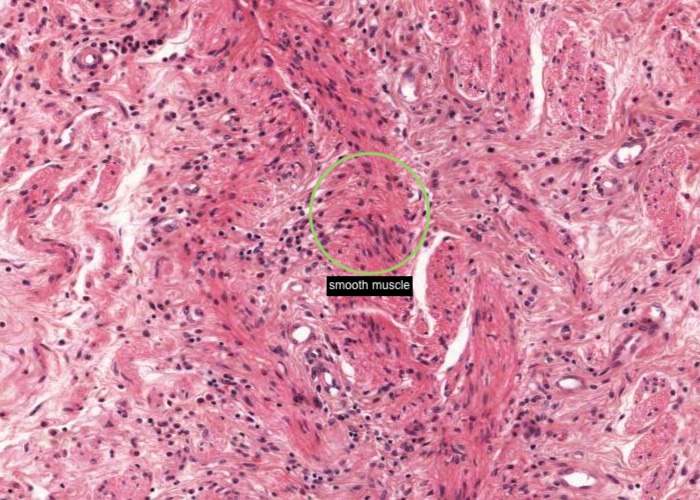

At low magnification, observe the three layers of the ureter: mucosa, muscularis and adventitia. This organization is maintained throughout the urinary passages. The mucosa of the ureter is thrown into characteristic longitudinal folds. It is made of transitional epithelium underlain by a layer of fairly cellular connective tissue (lamina propria). Quite a few lymphocytes are found in this lamina propria. The muscularis layer consists of two somewhat diffuse sheets of smooth muscle: the inner is longitudinal, and the outer is circular. Towards the bladder end it picks up a third oblique layer. This muscle produces peristaltic waves that push the urine to the bladder even when you are lying down. The adventitia is made of connective tissue and contains the nerves and blood vessels that supply the organ. One thing to note is that the ureter runs through loose connective tissue from the kidney to the bladder.

Connective tissue and smooth muscle make up the remainder of the wall of the ureter. The smooth muscle is in longitudinal and circular layers so when you examine the section see if you can pick out these longitudinal and circular layers of muscle.

The layers of the bladder are basically the same as in the ureter. However, the muscle layer is much thicker and includes a third sheet of smooth muscle with oblique orientation. Of course for a spherical organ like the bladder "longitudinal", "circular", and "oblique" are somewhat formalistic terms. In any case, sheets of smooth muscle running in different orientations are discernable although somewhat indistinct. The smooth muscle became “super contracted” when put in fixative. This has thrown the mucosa into pronounced folds. The epithelium also is over contracted in places. When you view this histological section find some nice views of rounded up umbrella cells with their acidophilic apical borders. Look further and you will come across patches of transitional epithelium in a relaxed state.